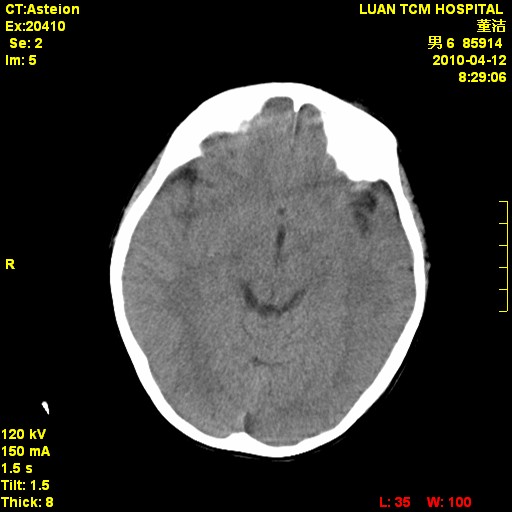

标题: PED3404:有结果,先猜猜这是啥病表现?男,12岁。 [打印本页]

标题: PED3404:有结果,先猜猜这是啥病表现?男,12岁。

考虑右侧额顶部颅内脑外血肿(edh可能)。

无病史无骨窗,无水肿无占位征象,右侧额顶部颅内血肿,或脑膜瘤。建议结合病史。

右侧额顶部自颅板向内近似半圆高密度影,周围无明显水肿,考虑:脑外血肿?脑膜瘤?淋巴瘤?